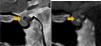

Se describe el caso de una adolescente de 14 años con antecedente de pubertad precoz central (PPC) en contexto de un micronódulo neurohipofisario. No presentaba otros síntomas y recibió tratamiento con análogos de GnRH. Ocho años después del diagnóstico, en un control anual realizado mediante resonancia magnética (RM) se objetivó que la lesión reportada como micronódulo en realidad tenía origen óseo, dependía de la silla turca y no afectaba visiblemente a la glándula hipofisaria ni a otras estructuras (fig. 1). Este hallazgo coincidió con una modificación en nuestro hospital del protocolo de secuencias radiológicas hipotálamo-hipofisarias y se confirmó con tomografía axial computarizada (TC) (fig. 2).

La espina selar (ES) es una prominencia ósea localizada en el centro del dorso de la silla turca y que protruye anteriormente. Se considera una rara malformación congénita con una incidencia de 1:5000-1:8000 cuyo origen es un remanente notocordal1. Puede deformar estructuras cerebrales dando síntomas por compresión y/o desplazamiento, habiéndose relacionado con PPC, diabetes insípida, hipopituitarismo, síndrome de Cushing, cefalea y hemianopsia bitemporal1–3. Es difícil diferenciarlo de una lesión intrahipofisaria, precisando realizar cortes finos en secuencias específicas de RM o estudio TC para demostrar su continuidad con la silla turca2. En nuestro caso, dado que no se observan otras alteraciones hipotálamo-hipofisarias, consideramos que la ES puede ser la causa de PPC. El tratamiento es médico para corregir los déficits endocrinológicos y quirúrgico si ocasiona síntomas graves3. Está descrito el crecimiento de la ES, por lo que se debería realizar seguimiento clínico y radiológico1.